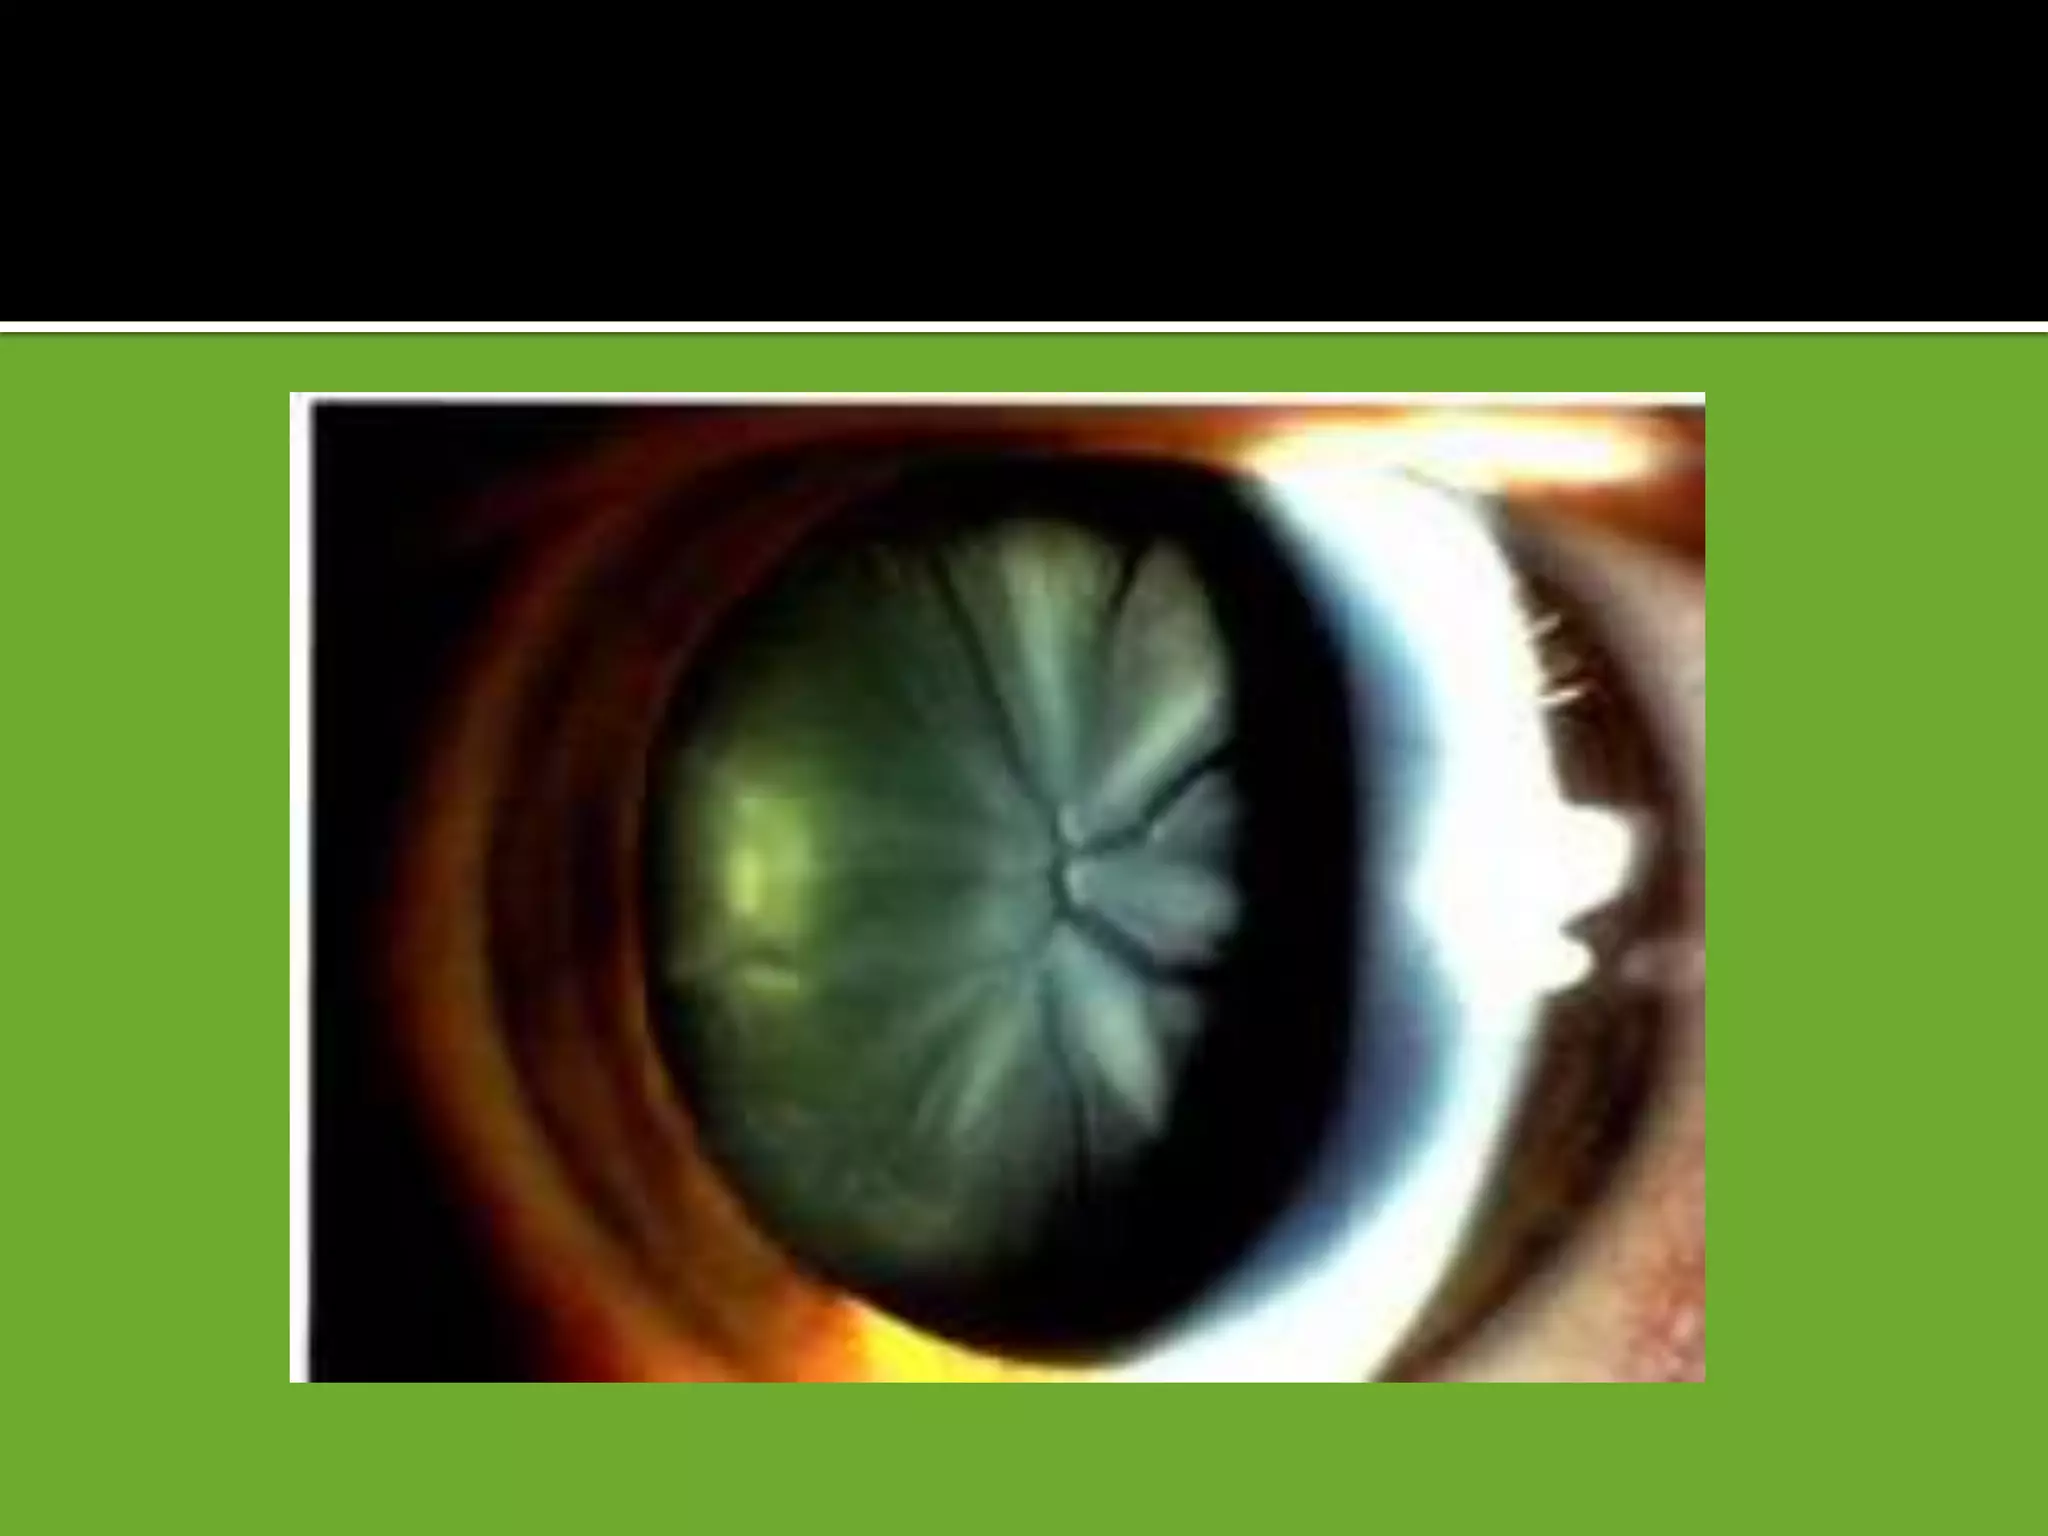

1 Penetrating trauma

2 Blunt trauma may cause a characteristic flower-shaped

opacity

 A ring-shaped anterior subcapsular opacity may underlie a Vossius

ring [. Imprinting of iris pigment on anterior lens capsule]

 Commonly opacification occurs in the posterior subcapsular

cortex along the posterior sutures, resulting in flower -shaped opacity